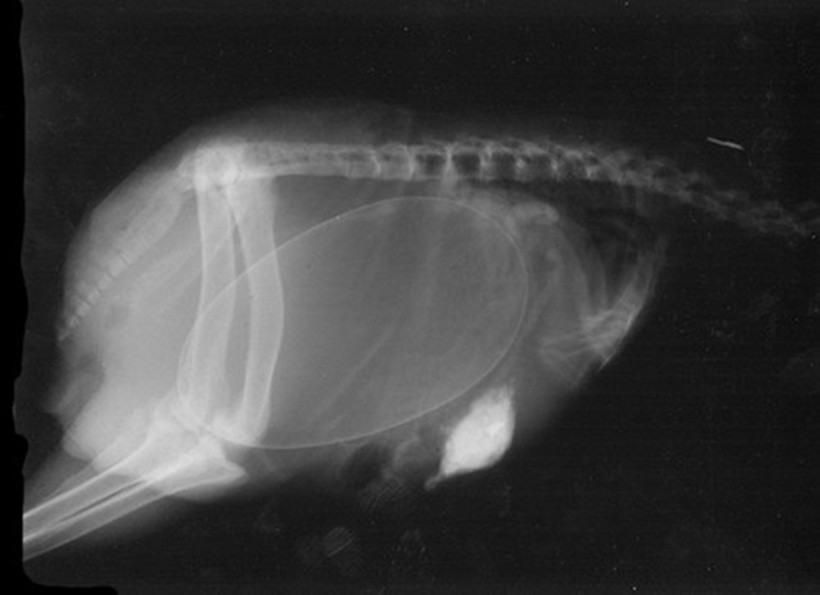

Птица киви в ожидании момента, когда можно будет отложить яйцо с птенцом